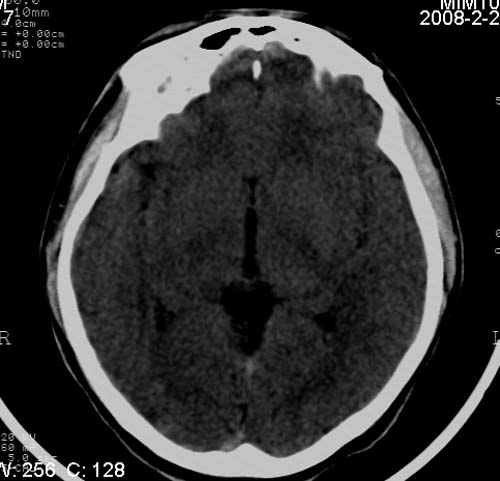

男,17岁,3天前与人斗殴,自述头痛、头晕。无恶心、呕吐,无阳性体征,一般情况良好。

病灶以钙化为主,无明显占位效应,病灶周围无水肿,这种情况应该是脑血管畸形,最多见的是动静脉畸形,其次是海绵状血管瘤.

考虑为:右侧顶叶脑血管畸形。建议:行进一步检查明确诊断。

考虑右侧顶叶脑血管畸形;avm可能性大。建议:mri检查。

病人较年轻,有头疼、头晕症状,动静脉畸形可能性大。